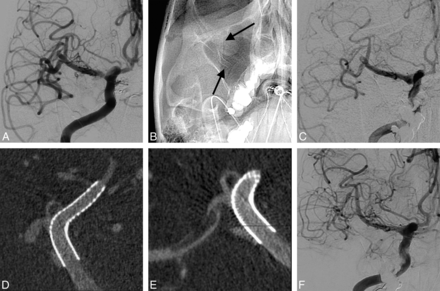

A 44-year-old woman who presented with an incidentally found aneurysm was treated in our institution. Although the aneurysm was small, the patient requested treatment. A, The right internal carotid angiogram shows a saccular MCA bifurcation aneurysm. B, The unsubtracted view after FDS placement in the superior bifurcation branch. C, The final internal carotid angiogram confirms the partial thrombosis but shows very good collateral flow. After stent delivery, VasoCT curved reconstructions of the superior (D) and inferior branches (E) show good patency of the FDS but immediate partial thrombosis in the covered branch and aneurysm. The patient was kept under a double dose of antiplatelet therapy, heparin, and noradrenaline for 48 hours. She did not develop any symptoms, and early follow-up DSA showed the normal aspect of the covered branch. However, the angiogram obtained at 2-year follow-up (F), demonstrates asymptomatic complete occlusion of both the covered branch and aneurysm.